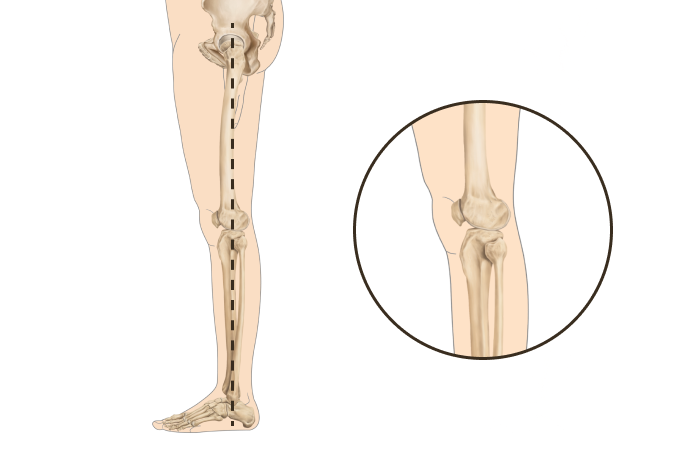

다리의 각도와 회전에 따라

경사형 휜다리

발의 변형이나 요족 및 걸음걸이 이상으로 무릎에 비정상적인 힘이 작용하며 생김

회전형 휜다리

고관절과 무릎이 내회전되어 발,발목 변형 동반되는 경우가 많고, 척추와 골반이 함께 틀어짐

복합형 휜다리

전면은 회정형 원다리처럼 보이나 경사형과 회전형 원다리 특징을 모두 가진 형태

특발형 휜다리

특발성측만증을 동반하거나 사고로 인한 경우 또는 다리 길이 차이 등 구조적 문제를 동반

왜 당당의 휜다리 회전교정일까요?

휜다리는 단순히 무릎 사이 간격이 벌어진 것이 아닙니다.

무릎 위의 대퇴골과 아래의 정강이뼈가 회전하면서 무릎까지 뒤로 빠지기 때문에 다리사이 간격이 넓어지는 겁니다.

당당 휜다리

발(아치)-발목-무릎관절-고관절-골반의 서로 다른 회전을 바로 잡는 기술입니다.